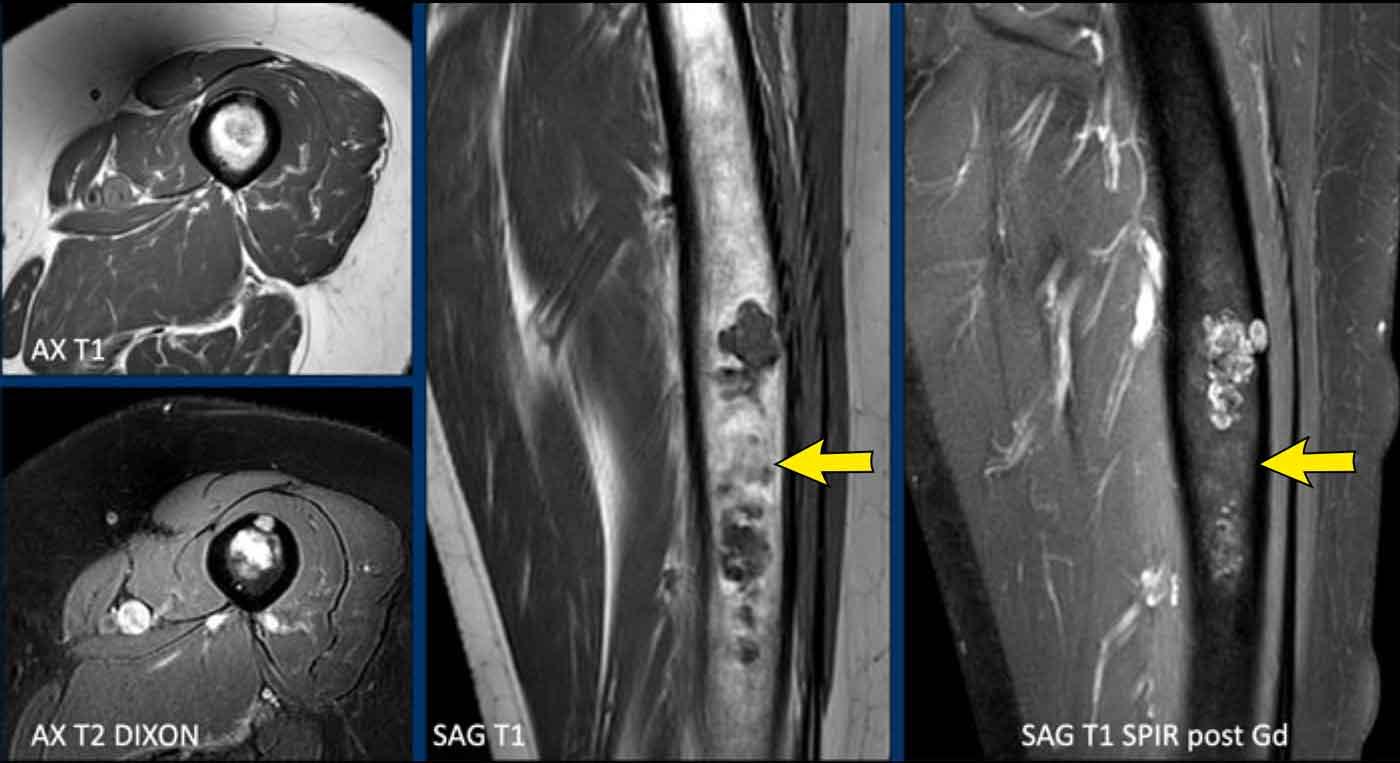

Trường hợp này đã được trình bày trước đây.

Nhìn lại hình ảnh MRI trước đó được thực hiện 5 năm trước, tổn thương đã tăng trưởng 6 mm theo chiều sọ-đuôi.

Cũng lưu ý sự mở rộng của tổn thương về phía trước (mũi tên vàng).

Không có hiện tượng mỏng vỏ xương, phù tủy xương hay viêm màng xương.

This lesion is an

ACT and remains in follow-up.